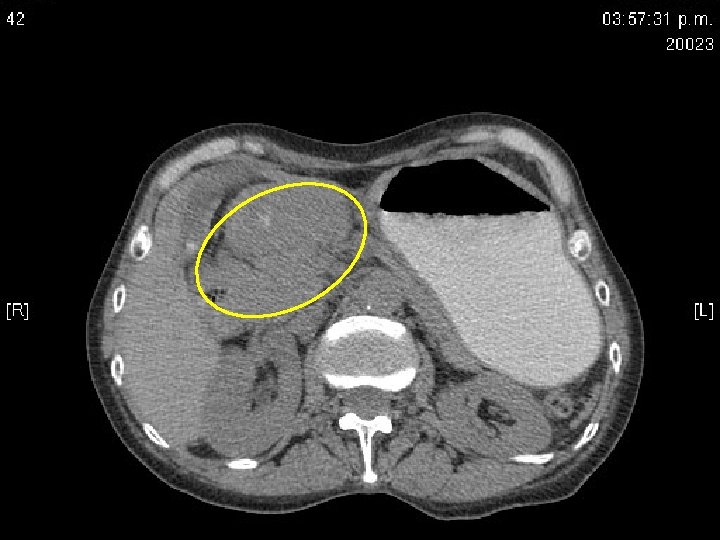

Tomografía abdominal • Hígado con presencia de nódulo de 10 mm en el segmento 3. • Estómago distendido con abundante contenido liquido en el fondo con paredes gruesas a nivel del antro de 12 mm que condicionan estrechez de la luz, infiltran duodeno. • Infiltración de la grasa perigástrica que infiltra páncreas. No se definen adenopatías adyacentes. • CC: quiste hepático. NM gástrico con infiltración a páncreas y grasa perigástrica, cabeza de páncreas prominente.

TAC: signos tomográficos